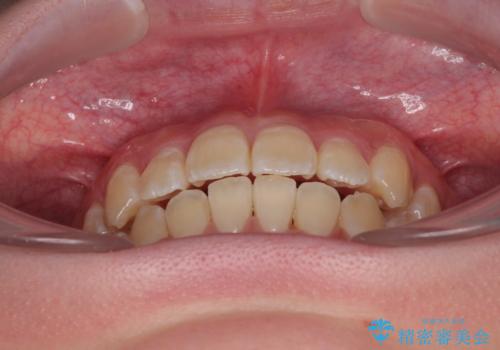

- 「前歯のデコボコ(叢生)をきれいに整えたい」とのことでご来院されました。

患者様の協力もあり、およそ1年間で治療を完了。スムーズな歯の移動を実現しました。

上下の正中(真ん中のライン)もずれることなく、バランスの取れた美しい歯並びに。笑顔に自信を持てる仕上がりとなりました。